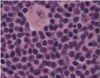

What disease is indicated by this bone marrow biopsy?

Mantle Cell Lymphoma

See numerous small lymphocytes with mixed in pink histiocytes (tissue macrophages).